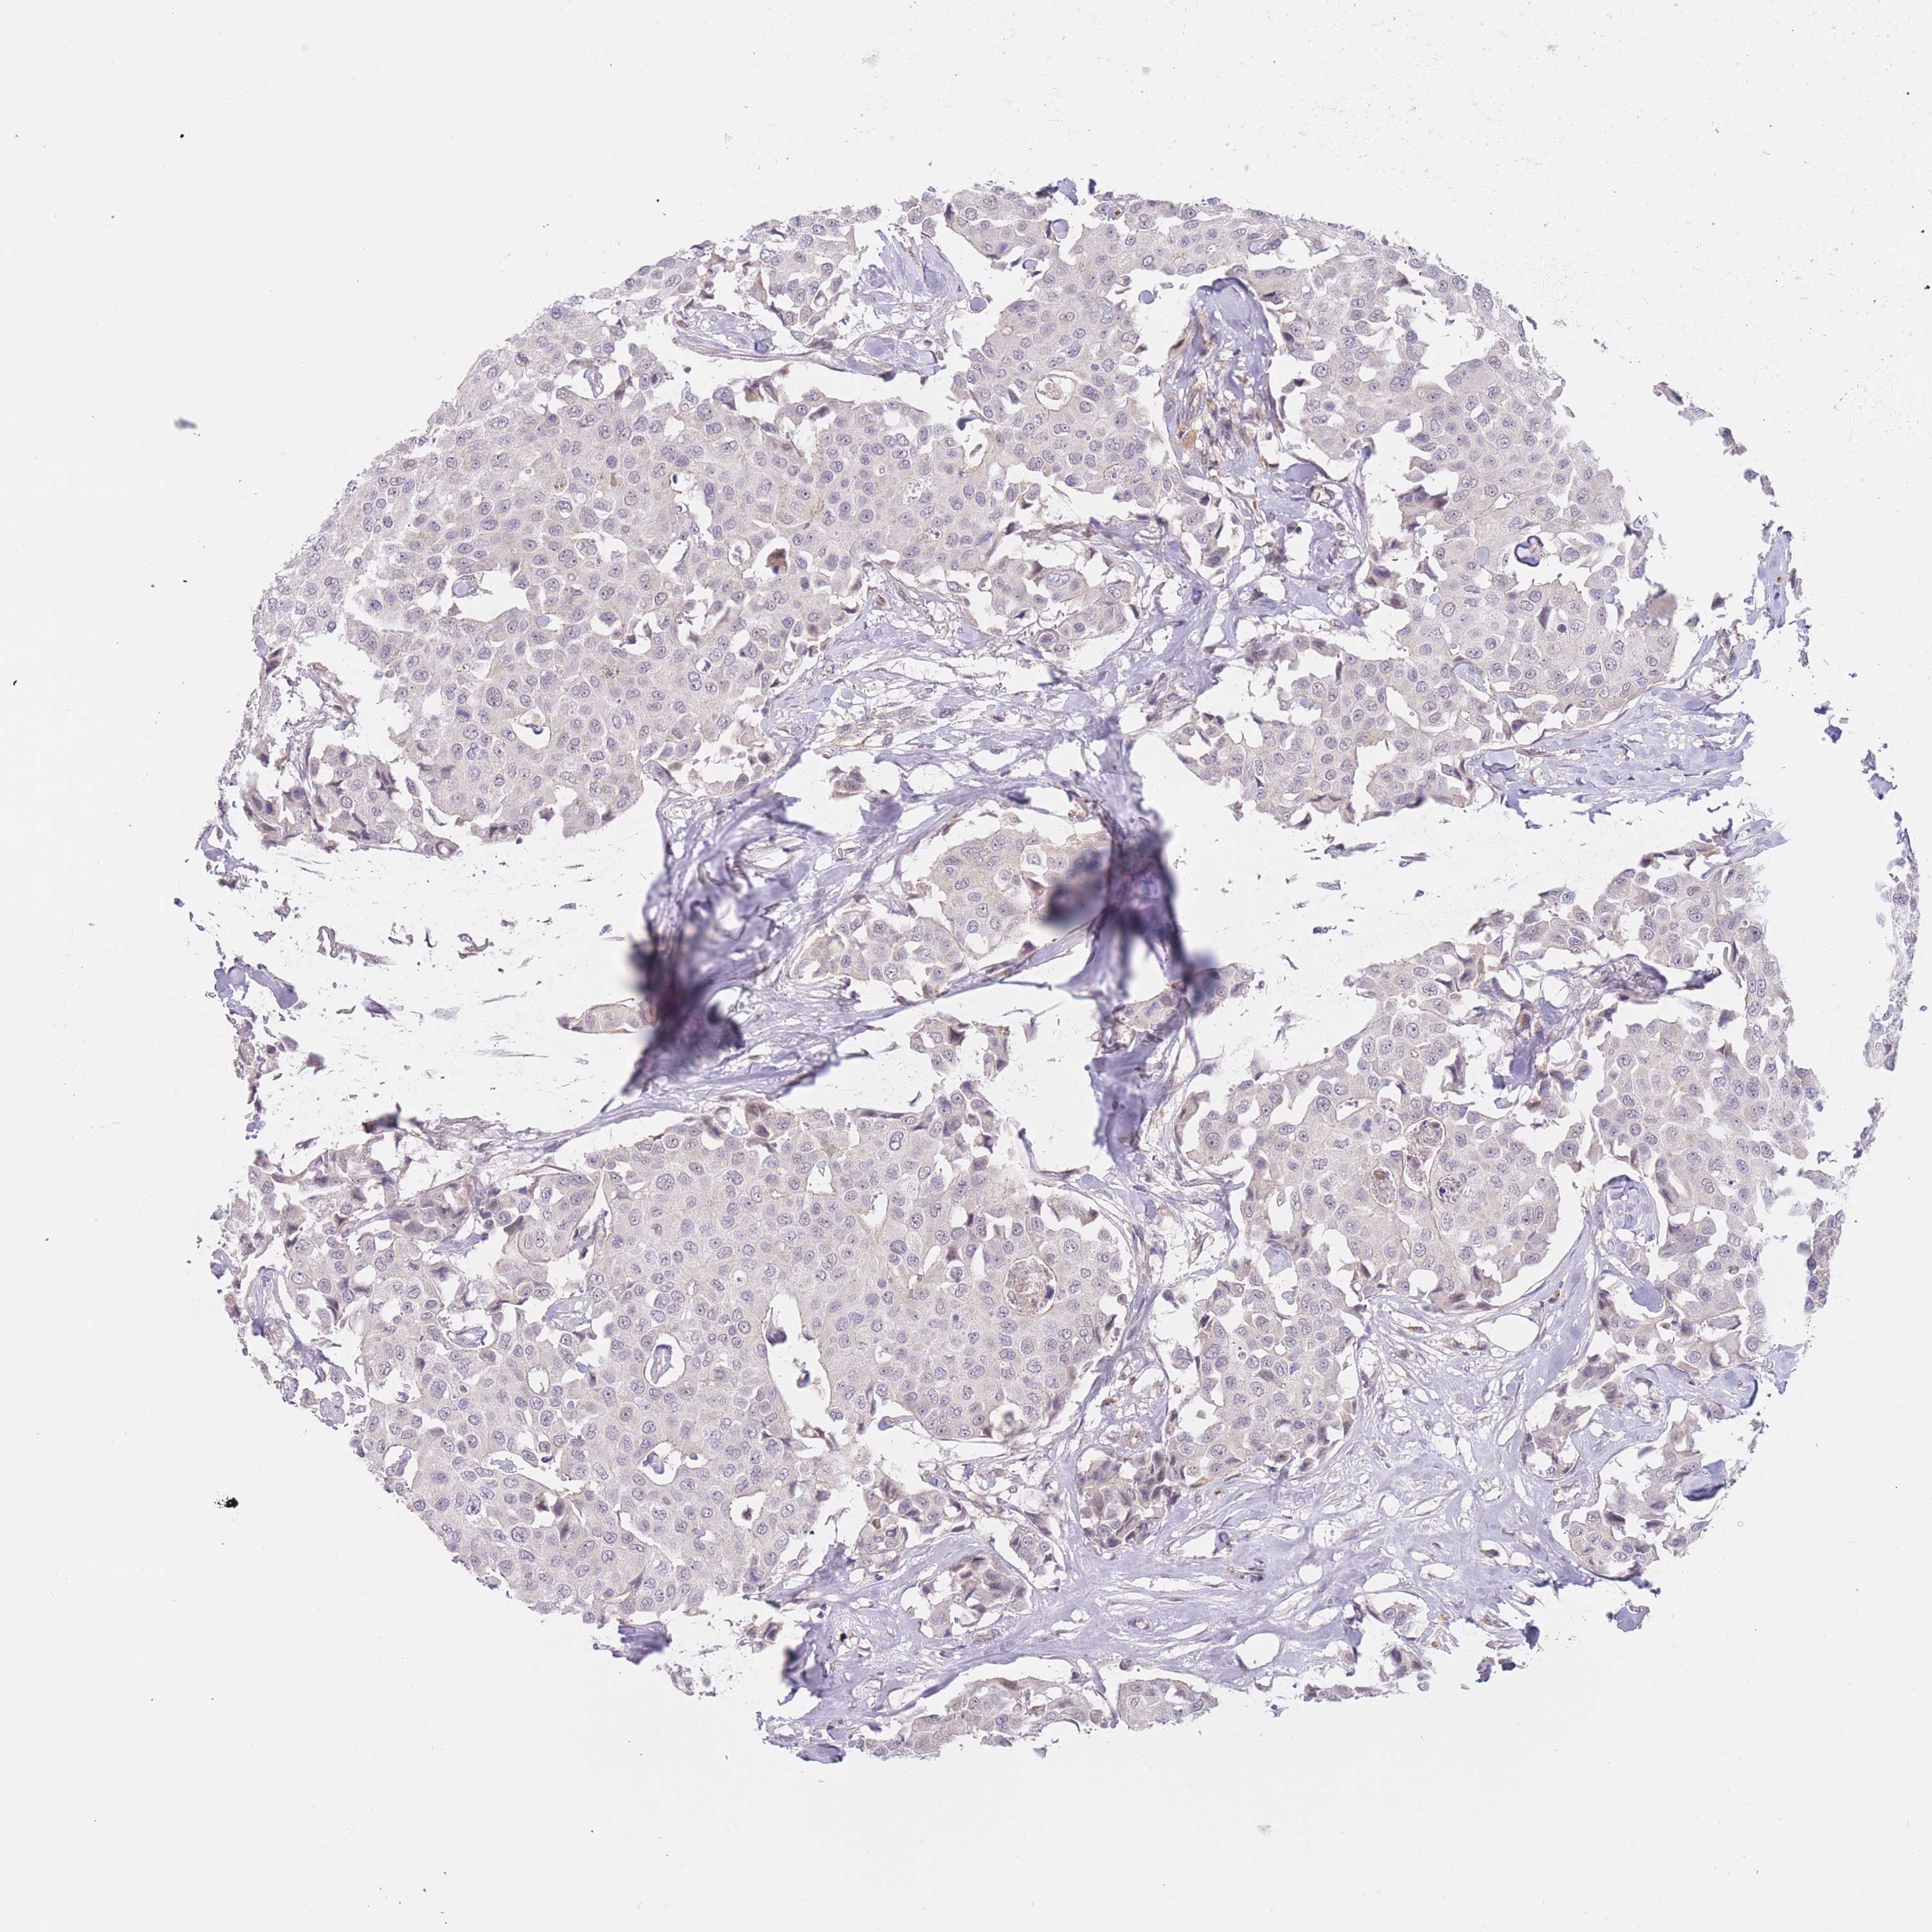

FUT6

CANCER BREAST CANCER Show tissue menu

BRCA TCGA BRCA VALIDATION PROTEIN EXPRESSION

Breast cancer

Human cancer

FUT6 is not prognostic in Breast Invasive Carcinoma (TCGA)